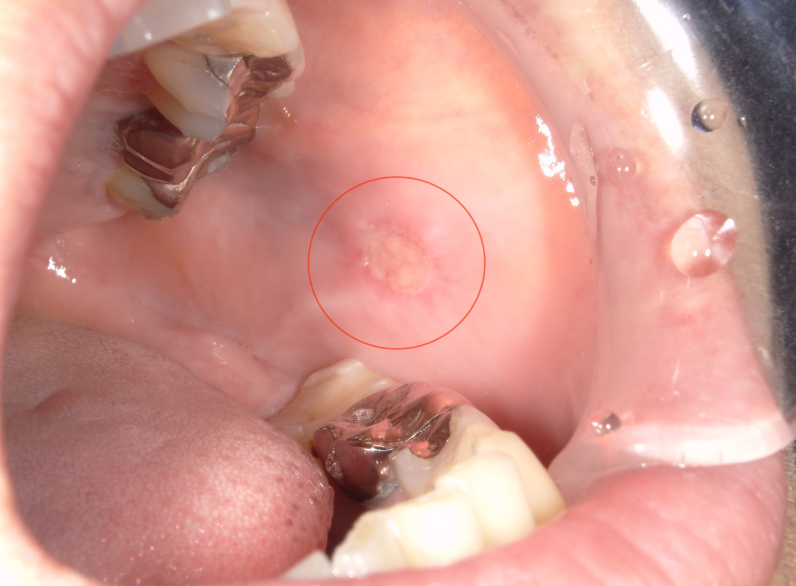

口内炎画像 (312 無料画像)

口内炎画像